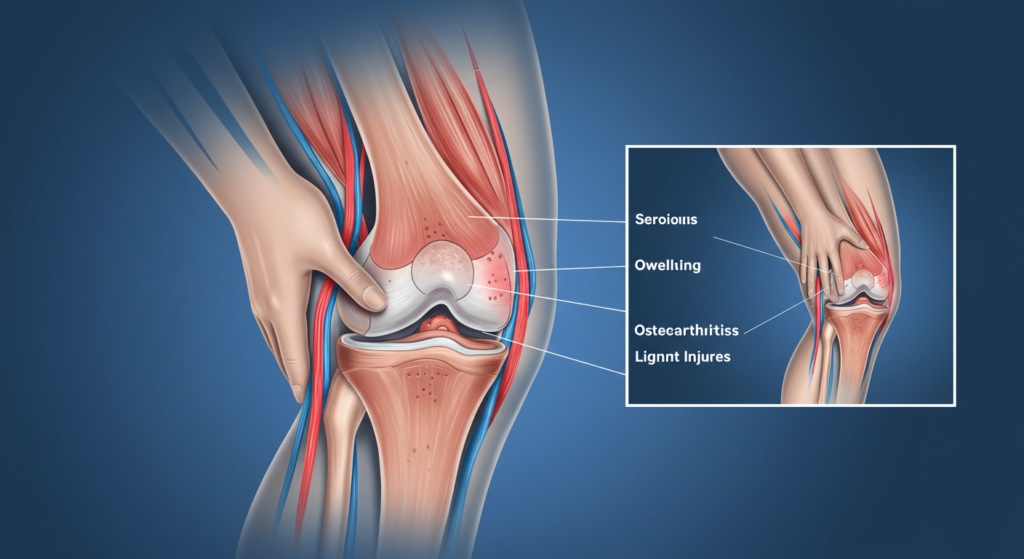

Jika sakit lutut tidak berkurang walaupun selepas berehat atau mengambil ubat tahan sakit, ini mungkin menandakan masalah yang lebih serius seperti arthritis atau kecederaan pada struktur lutut. Contohnya, seseorang yang mengalami osteoarthritis mungkin merasakan kesakitan yang berterusan di lutut, terutama ketika bergerak atau melakukan aktiviti fizikal. Jika sakit lutut semakin teruk dan tidak berkurang dengan rawatan asas seperti rehat dan terapi haba, ia boleh menjadi petanda bahawa lutut mengalami kerosakan yang lebih serius dan memerlukan pemeriksaan lanjut oleh pakar perubatan.

Bengkak yang berpanjangan pada lutut boleh menunjukkan berlakunya keradangan atau pengumpulan cecair dalam sendi lutut. Keadaan ini sering disebabkan oleh kecederaan ligamen atau jangkitan pada sendi lutut. Sebagai contoh, seseorang yang mengalami kecederaan meniskus akibat pergerakan yang salah semasa bersukan boleh mengalami pembengkakan yang berterusan di sekitar lutut. Jika bengkak tidak berkurang selepas beberapa hari atau menjadi lebih besar, ia mungkin menunjukkan keadaan yang lebih serius seperti bursitis atau sinovitis yang memerlukan rawatan segera.

Jika sakit lutut disertai dengan bunyi “klik” atau “pop” semasa bergerak, atau jika lutut terasa longgar dan tidak stabil, ia mungkin berpunca daripada kecederaan ligamen, seperti kecederaan ACL atau meniskus. Sebagai contoh, seorang atlet yang mengalami kecederaan ACL mungkin merasakan lututnya tidak stabil ketika berlari atau melompat, dan ini boleh meningkatkan risiko kecederaan lanjut. Jika sakit lutut menyebabkan kesukaran untuk mengawal pergerakan lutut atau menyebabkan rasa goyah semasa berjalan, adalah penting untuk mendapatkan pemeriksaan lanjut bagi mengelakkan kerosakan yang lebih teruk.

- Osteoarthritis – Kemerosotan tulang rawan lutut akibat penuaan boleh menyebabkan sakit lutut yang kronik. Keadaan ini berlaku apabila lapisan pelindung pada sendi lutut semakin menipis, menyebabkan geseran antara tulang. Individu yang mengalami osteoarthritis sering merasakan sakit lutut ketika berdiri lama atau berjalan jauh. ( Sumber: https://gleneagles.com.my/ms/medical-specialties/orthopaedic-trauma-surgery/knee-osteoarthritis)

- Kecederaan Ligamen – Kecederaan seperti kecederaan ACL sering berlaku dalam sukan yang melibatkan lompatan atau pergerakan pantas. Atlet yang mengalami kecederaan ini akan merasai sakit lutut yang tiba-tiba, diikuti dengan lutut yang bengkak dan sukar untuk bergerak.